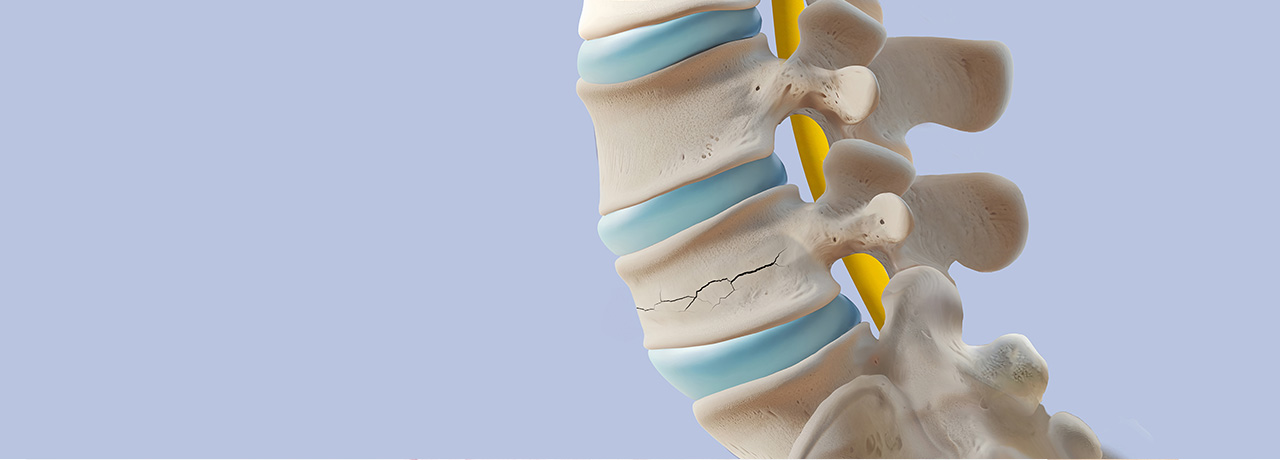

척추압박골절이란?

척추체성형술이란?